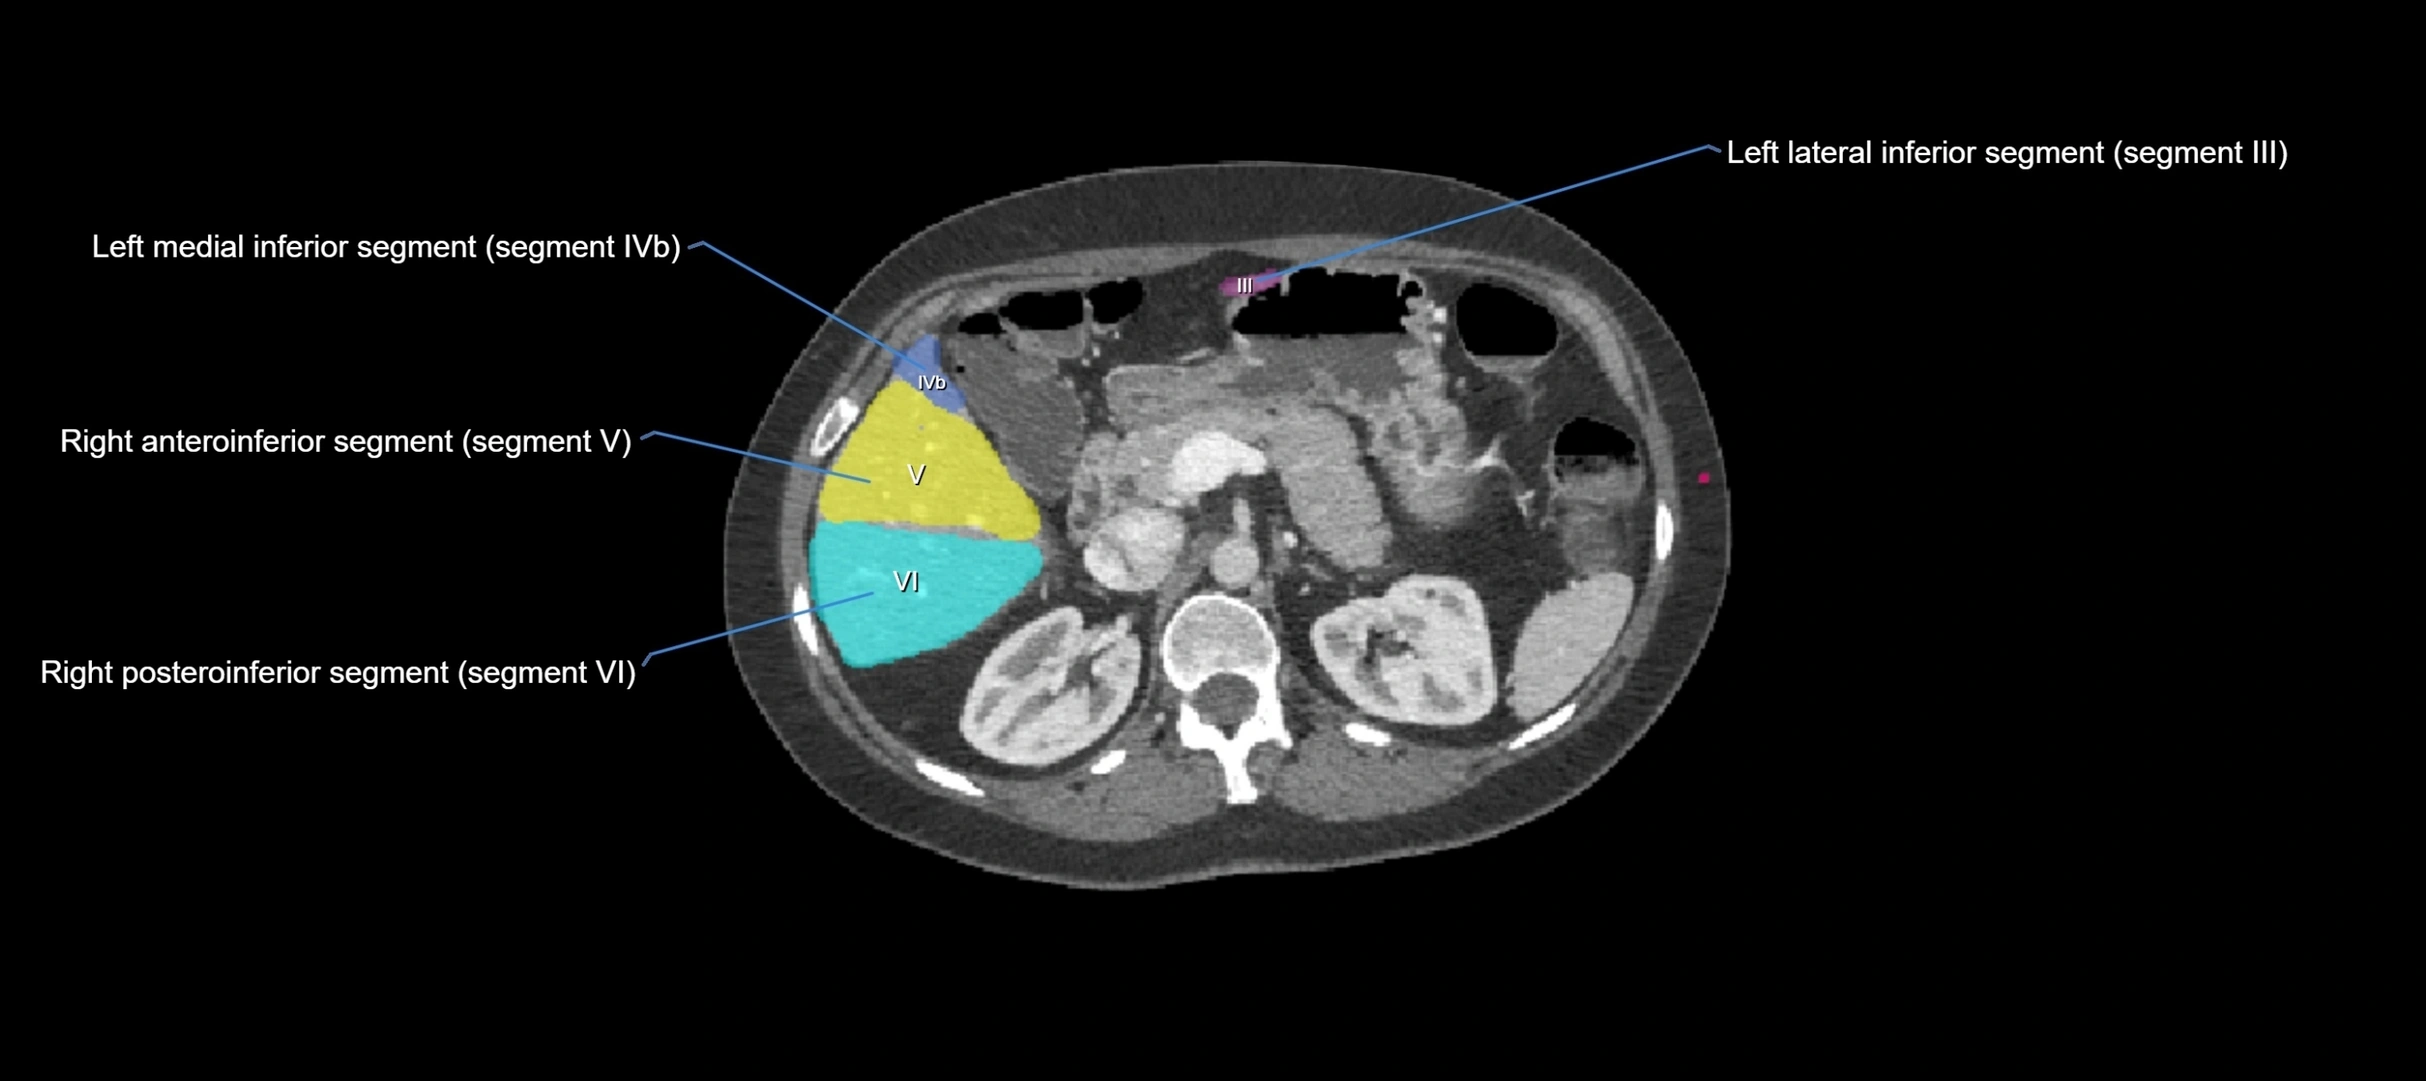

CT Image

image